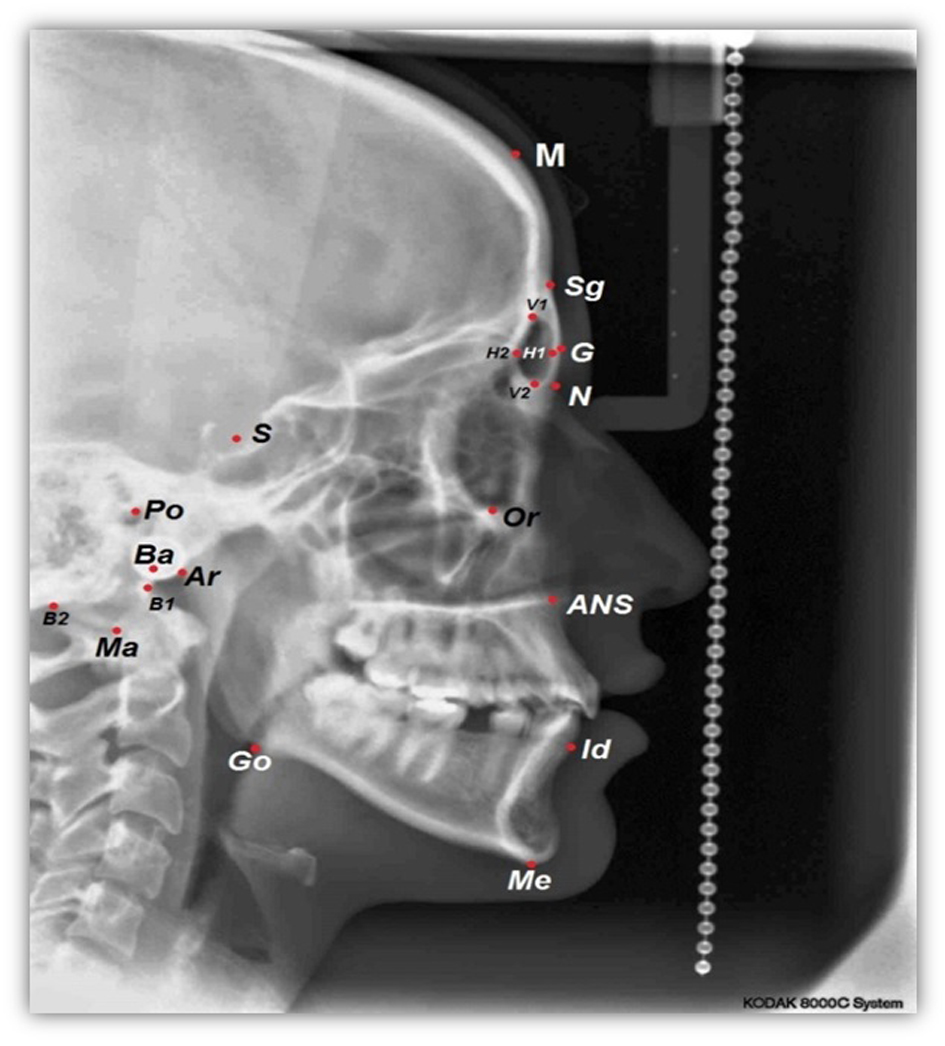

For each lateral cephalometric radiograph 19 craniofacial skeletal landmarks were digitized (Table 1 and Fig. 1) by one observer using a customized analysis created in Viewbox 4-Cephalometric Software (dHAL Software, Kifissia, Greece). Utilizing the selected and digitized landmarks, measurements that comprised 14 linear (Fig. 2), three angular (Fig. 3) and one proportional parameters were carried out (Table 2).

![]() Click for large image | Figure 1. A cephalometric radiograph illustrating the landmarks defined in Table 1. |